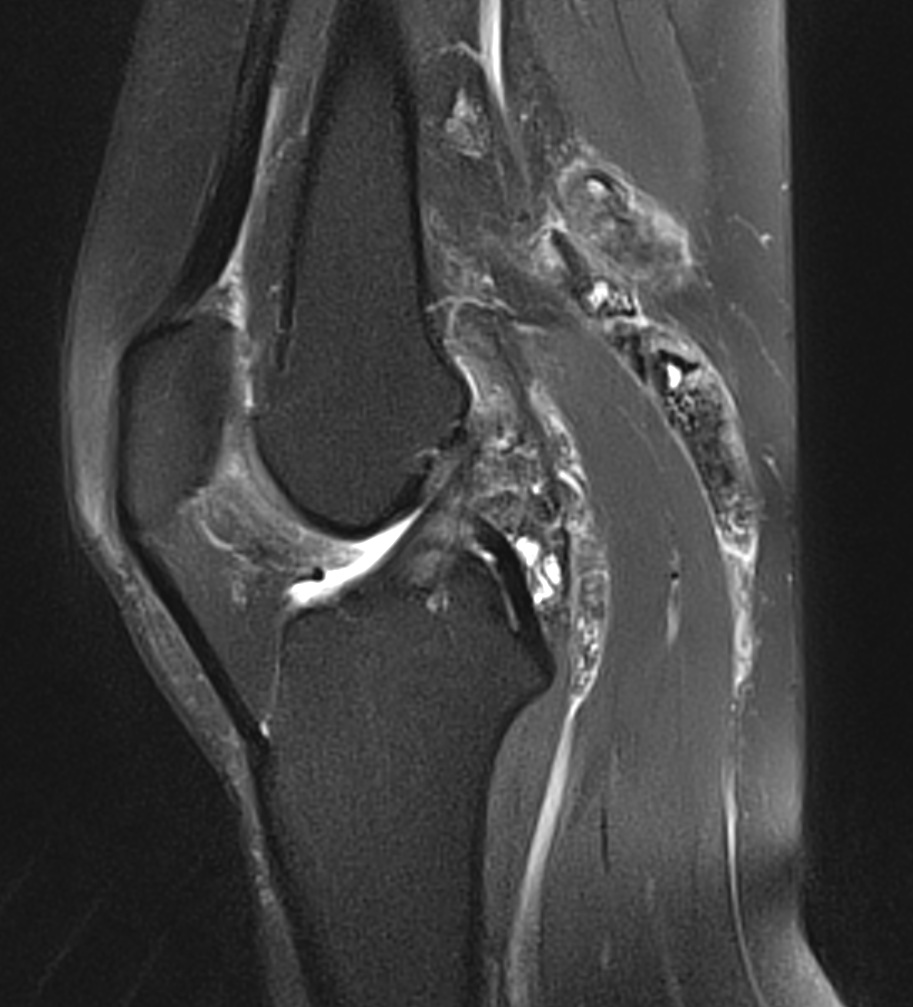

Synovite villo-nodulaire du genou 2